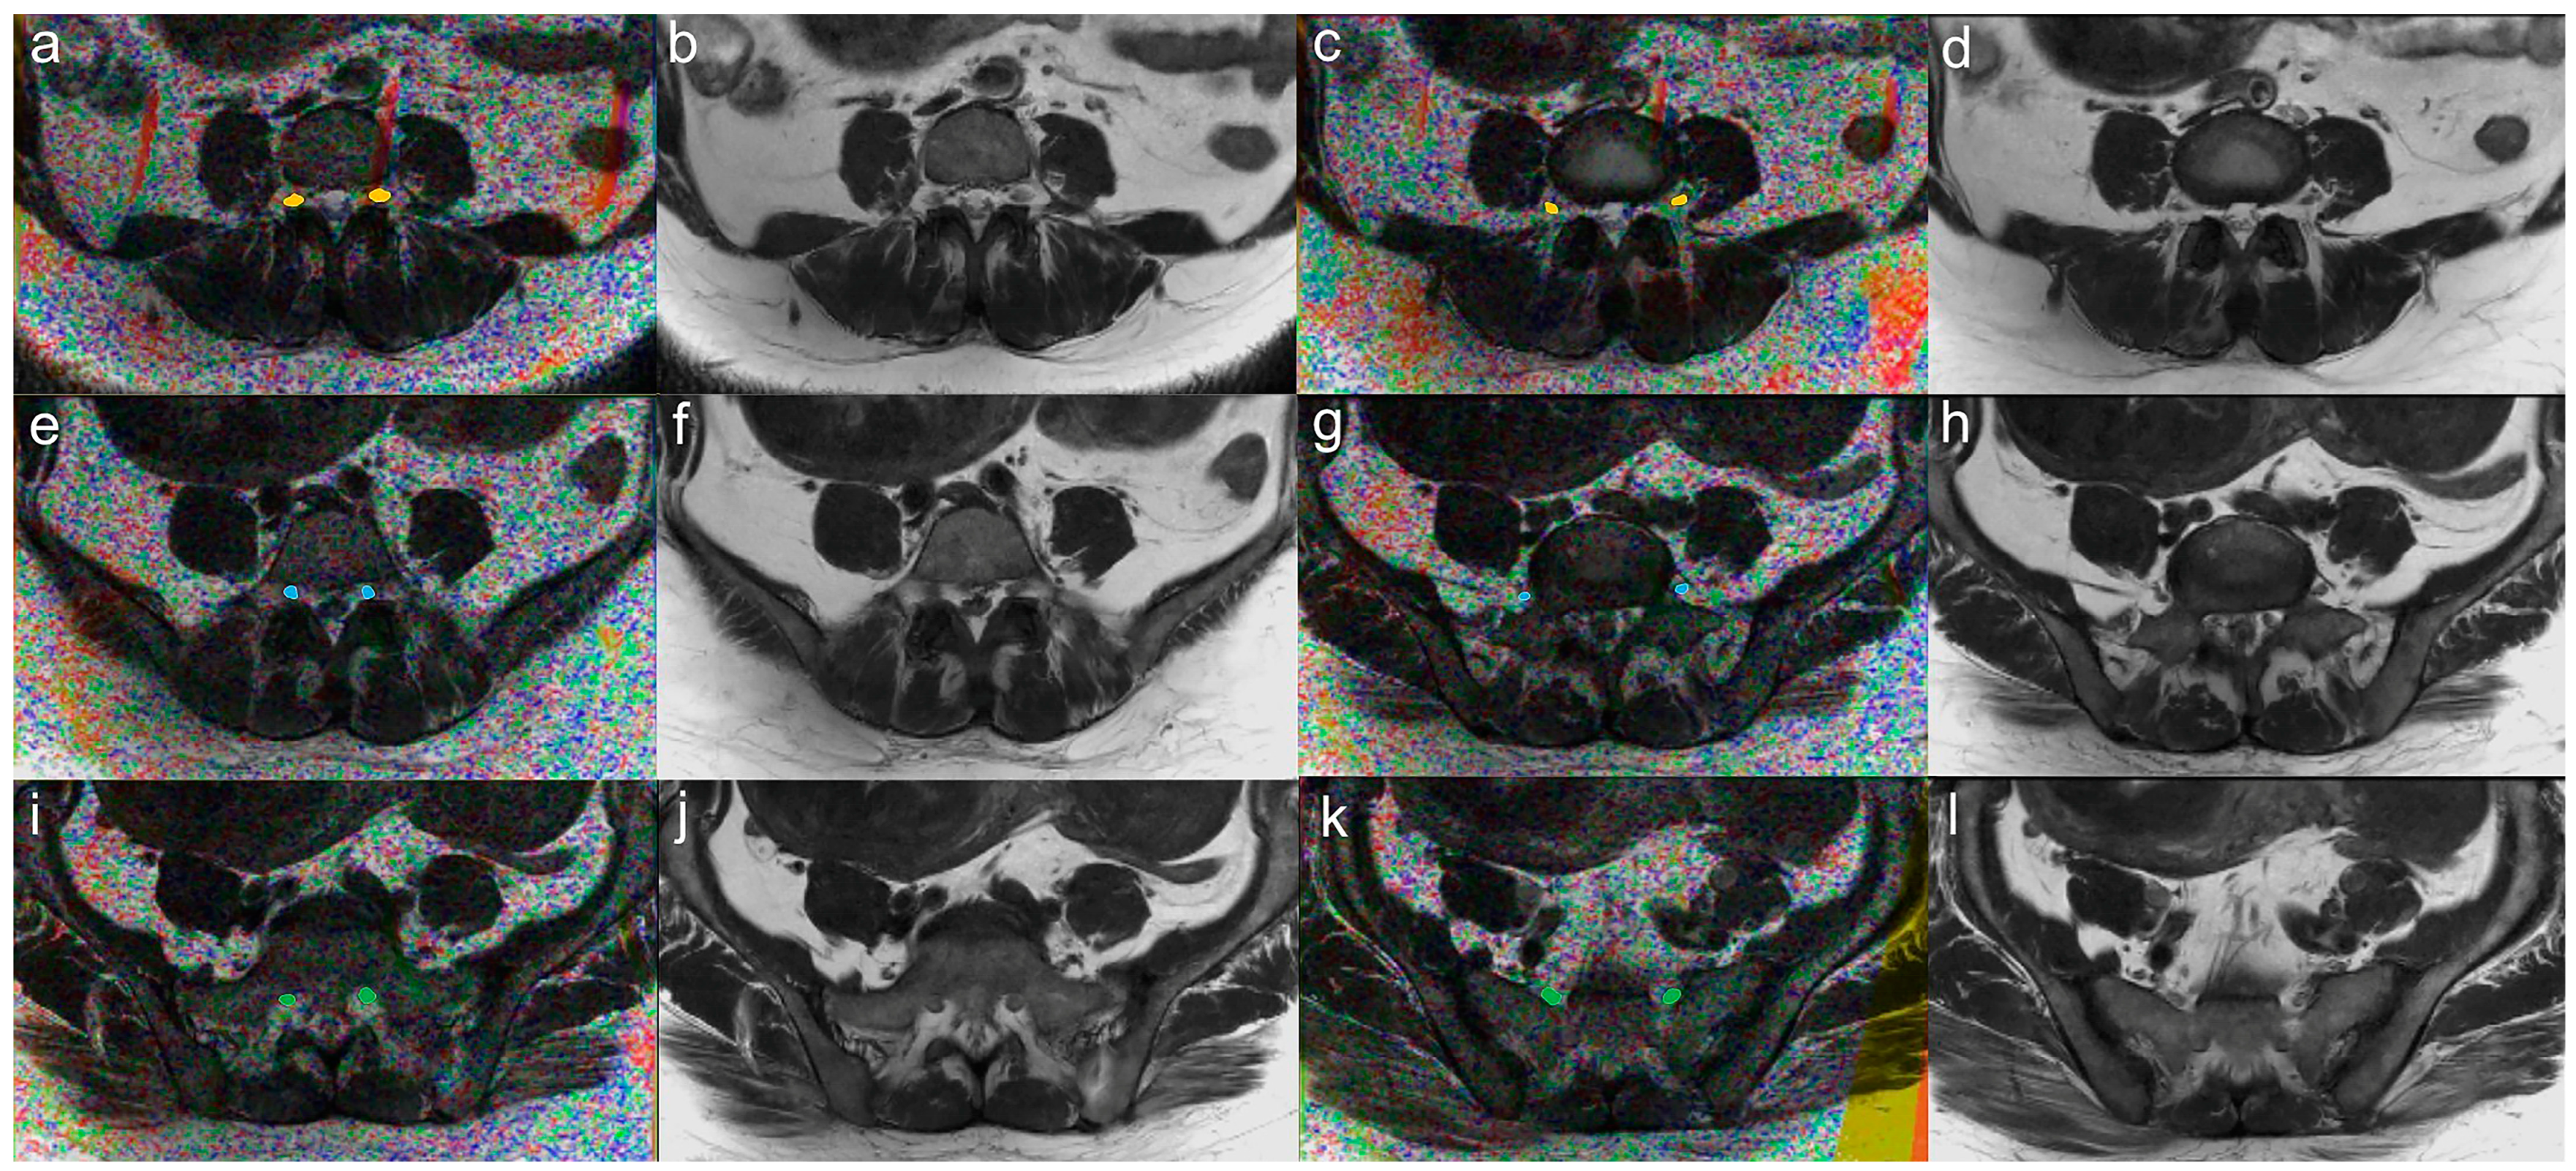

3.4. Evaluation of Diagnostic Performance